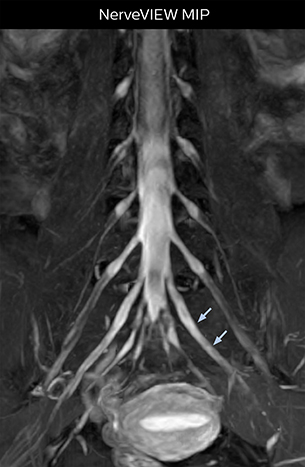

“In such case, we would then browse through axial T2-weighted MR images slice by slice and mentally reconstruct the actual situation based on both radiculography and MRI. Fortunately, NerveVIEW can now very well show nerve courses and presence of nerve compression or edema in one single image series.” “We have often seen NerveVIEW directly depict details of the nerve compression that were not observed by radiculography. Therefore, we think that with NerveVIEW we can reduce the number of invasive examinations, especially for some patients with lumbar plexus symptoms.”

The key concept in MR neurography, Dr. Yabuki stresses, is the ability to directly visualize spinal nerves, versus inferring the presence of pathology indirectly. “Before NerveVIEW, we estimated compression of the nerve by looking for the presence or absence of fat signal on other MR images,” he says.

“For example, in sagittal images, when the presence of fat is observed in the intervertebral foramen, it suggests that there is a margin around the nerve. Similarly, the absence of fat indicates that the nerve is being compressed. So, we used to deduce nerve compression indirectly. With NerveVIEW, however, we can observe the condition of the nerves directly, regardless of the presence or absence of fat. We always prefer such direct observation of anatomy over having to make an inference about it.”

“The intra-luminal signal of veins, especially around the intervertebral space, can be suppressed well with NerveVIEW. As a result, we can easily observe the detailed nerve structure around the posterior ganglion,” he says. “This is why we use 3D NerveVIEW for intraforaminal stenosis and extraforaminal stenosis/herniation (lateral disc herniation). On the other hand, if herniation is suspected to exist inside the dorsal root ganglion (DRG), balanced TFE or ProSet-FFE is applied. NerveVIEW is not suitable for evaluating the median type of herniation.” The SE-EPI DWI-based method for MR neurography works well for large FOV exams like whole-body MRI, but focal examination of nerves is often limited by the attainable spatial resolution (both inplane and slice direction) and geometric distortion. “3D NerveVIEW achieves higher in-plane resolution – close to our other routine spine sequences – and the source images can be used instead of adding a fat-suppressed T2-weighted sequence,” Tanji says.

According to Tanji, methods such as ProSet FFE, STIR or 3D VISTA are anatomically nonselective because background signals, for instance from blood vessels, often interfere with nerves, which hampers evaluation of details, especially at the peripheral side of the nerves.

“NerveVIEW can clearly show nerve courses and presence of nerve compression. However, when multiple abnormalities are seen, it can still be hard to determine which nerve is causing the symptoms,” says Dr. Yabuki. “In our experience so far, we see abnormal findings on NerveVIEW in about 70% of elderly patients. As the pain is usually caused by only one nerve, we thus need to find the exact corresponding nerve.” “With a nerve root block, the patient's pain is improved by infiltration of local anesthesia directly around the nerve root considered to be responsible. Knowing such nerve root block findings prior to image interpretation, helps to easily recognize abnormal findings on NerveVIEW as well. In other words, without a priori knowledge, based on symptoms and/or nerve root block findings, we must be aware of the possibility of overdiagnosis.”